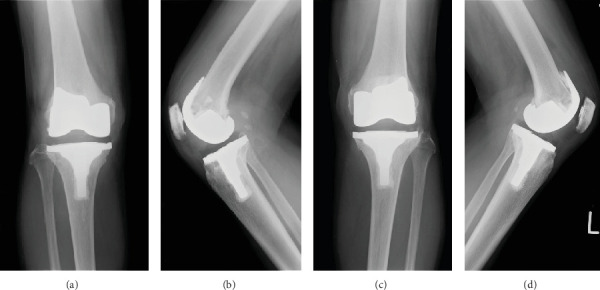

我们报告一个不寻常的病例腱鞘巨细胞瘤(TGCT)的患者谁接受了全膝关节置换术(TKA)内侧膝骨关节炎滑膜骨软骨瘤病(SO)。一位72岁的女性接受了传统的基于夹钳的双侧双交叉肌稳定TKA。术后四年,患者以仅右膝持续性疼痛为主诉来我院就诊,并伴有复发性自发性关节出血。我们进行了滑膜切除术,开放切除清创和聚乙烯交换。滑膜标本的组织学分析与TGCT一致。我们报告第一例TKA后SO背景下发生的新生TGCT的影像学和病理细节。

We report an unusual case of a tenosynovial giant cell tumor (TGCT) in a patient who received a total knee arthroplasty (TKA) for medial knee osteoarthritis with synovial osteochondromatosis (SO). A 72-year-old woman underwent conventional jig-based simultaneous bilateral bicruciate-stabilized TKA. Four years after the surgery, she came to our hospital with a chief complaint of persistent pain in the right knee only, with recurrent spontaneous hemarthrosis. We performed a synovectomy with open excisional debridement and a polyethylene exchange. Histologic analysis of synovial samples was consistent with TGCT. We present the imaging and pathological details of the first case of de novo TGCT that occurred in the background of SO after TKA.